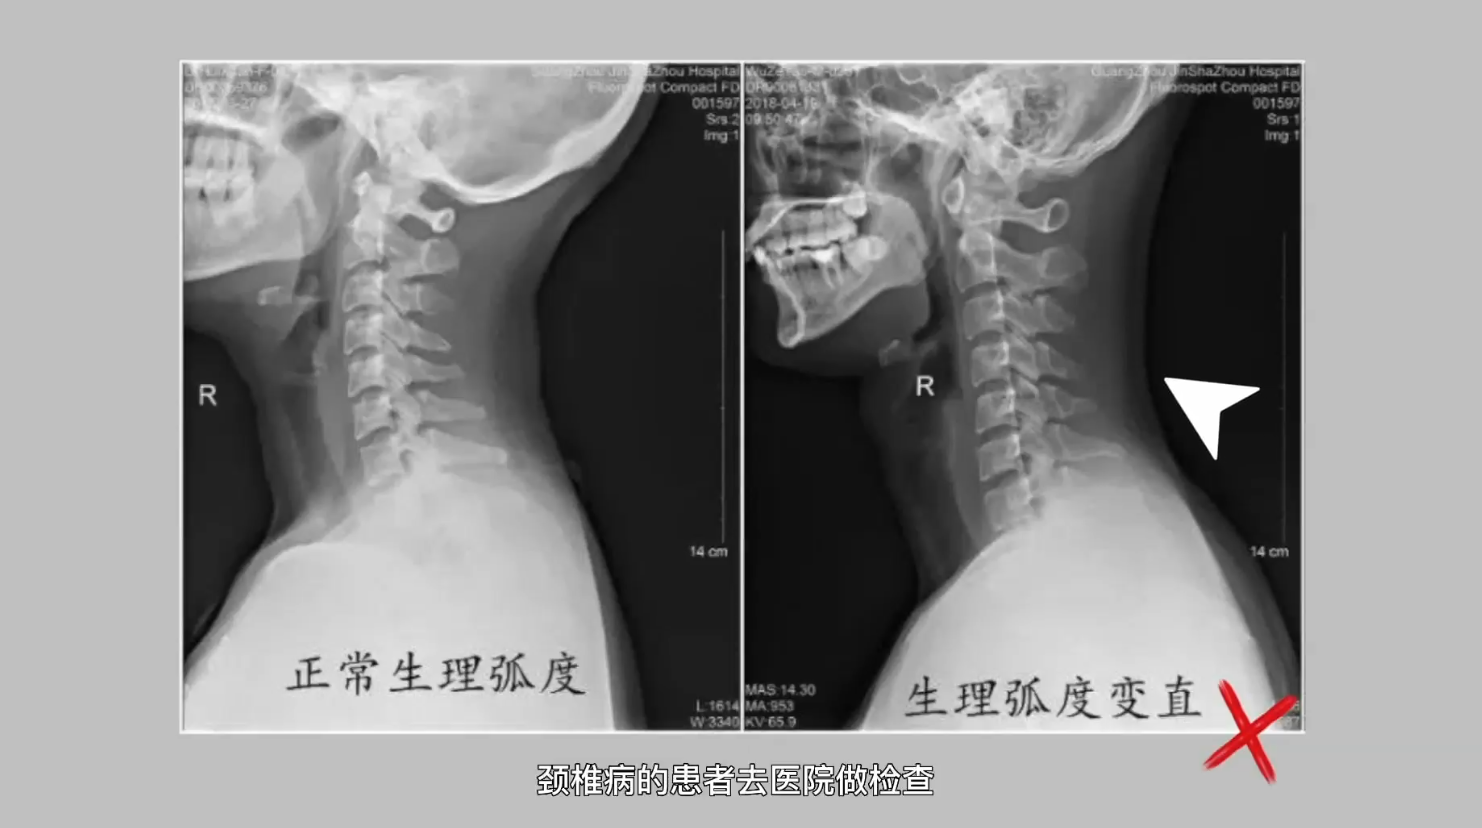

脊柱是由颈椎、胸椎、腰椎、骶椎、尾椎共32个椎体,通过23个富有弹性的椎间盘和很多活动方向不同的小关节,以及长短不等的坚强韧带连结而成的。它上连颅骨,中部与肋骨相连,下端和髋骨组成骨盆。正常人的脊柱自上而下有4个像弹簧样的生理弯曲,从侧面看呈S形,即颈椎前凸、胸椎后凸、腰椎前凸和骶椎后凸。

脊椎疾病一般是长期不良坐姿引起的,也可能是退行性病变、脊柱畸形导致的。脊椎疾病可以通过一般治疗、物理治疗、手术治疗的方式进行改善。